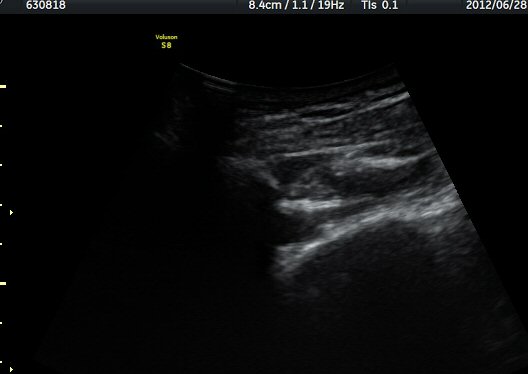

¿ª½Ã °ß°©°ñ °¡½Ãµ¹±â(spine) ¾Æ·¡¿¡¼­ Àú¿¡ÄÚ ³¶Á¾ÀÌ °üÂûµÈ´Ù(±×¸² 2). º¼·ÏŽÃËÀÚ·Î ¹Ù²Ù¾î °ü

ÂûÇÏ´Ï  °¡½Ãµ¹±â°üÀý¼ø°í¶û¿¡¼­ Àú¿¡ÄÚ ³¶Á¾ÀÌ ´õ¿í ¶Ñ·ÈÈ÷ °üÂûµÈ´Ù(±×¸² 3, 4).